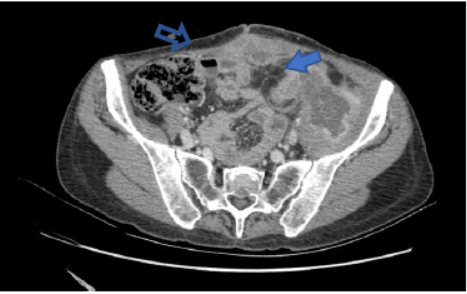

Una nueva TC de estadificación demostró la infiltración del tumor al músculo ilíaco y nervio crural izquierdo. La arteria ilíaca externa se encontraba en íntimo contacto sin invasión aparente. Se objetivó una colección sobre la pared abdominal con relación a la cicatriz mediana (Fig. 1). No había evidencia de diseminación a distancia. Los marcadores tumorales CEA y CA 19-9 fueron normales.

Fig. 1: a) Engrosamiento del colon descendente con fístulización hacia el músculo ilíaco izquierdo y colección en su interior (flecha sólida). b) Colección detrás de la mediana (flecha vacía).